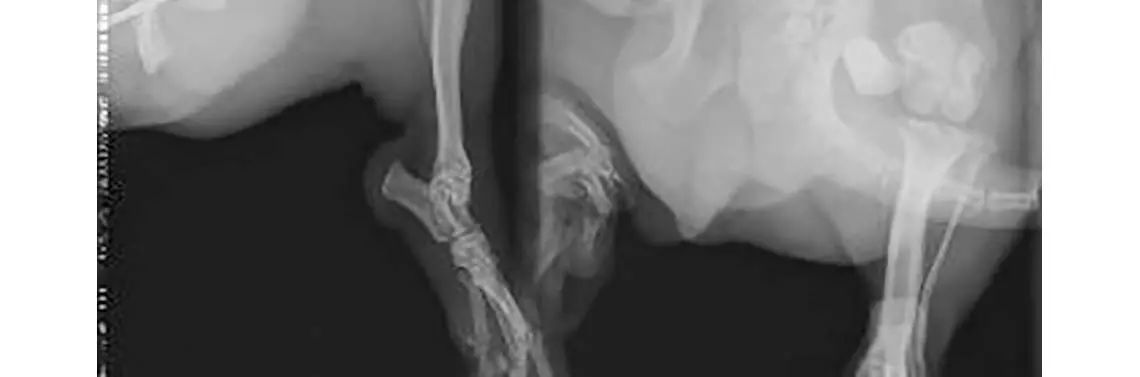

Pies, rasy pekińczyk, samiec, w wieku 4 lat, prawdopodobnie uległ wypadkowi samochodowemu, na skutek którego doszło do złamania 1/3 dalszej lewej kości udowej. Złamanie zamknięte, proste, o skośnej szczelinie przełomu, z przemieszczeniem bocznym oraz skróceniem odłamów (fot. 1).

RTG boczne i strzałkowe złamania kości udowej